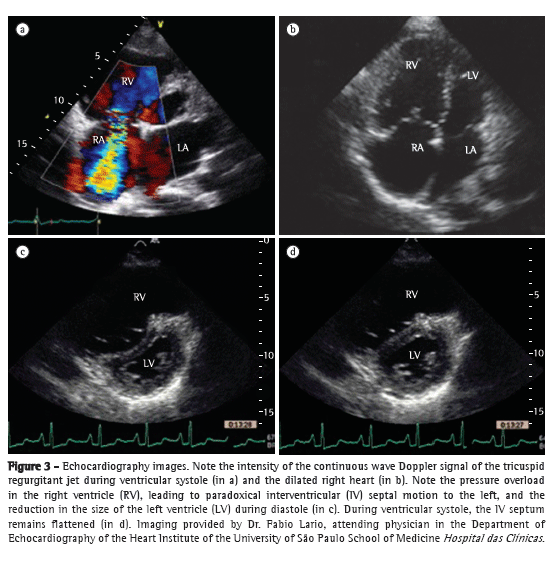

However, RV ejection fraction and volumes cannot be calculated with the use of the mathematical equations usually employed to study the LV. Therefore, several echocardiographic parameters have been developed to assess RV function and the hemodynamics of the pulmonary artery. The most widely used of those methods is based on the identification of tricuspid regurgitation (TR). Measurement of TR provides an estimate of the pressure gradient in the right heart. The first studies involving continuous wave Doppler echocardiography were published in the mid-1980s.(9,10) The technique consists of measuring peak velocity of tricuspid regurgitation (VTR), which provides an estimate of the regurgitant flow from the RV to the right atrium (RA), as shown in Figure 3. With the use of the simplified Bernoulli equation (∆P = 4 × VTR2), it is possible to convert the flow measurement into an estimate of pressure. By adding this pressure gradient and an estimate of RA pressure, we obtain RV peak systolic pressure (RVSP), an approximation of the pulmonary artery systolic pressure (PASP), provided that there is no obstruction of the RV outflow tract. An RVSP > 35-40 mmHg is suggestive of PH.(10) In the presence of low regurgitant flow, the estimation of RVSP becomes less sensitive, because of the low signal intensity, which might lead to the underestimation of pressure values. However, the presence of extremely severe TR might also lead to the underestimation of pressure measurements, because equalizes the RA and RV pressures, resulting in a weak Doppler signal. Conversely, the method might also overestimate RVSP values.

Other echocardiographic parameters can also be used in the evaluation of PH. Measurement of TR at the opening of the pulmonary valve is used for estimating pulmonary artery diastolic pressure (PADP).(15) It is also possible to estimate pulmonary vascular resistance, which correlates with invasive hemodynamic measurement.(16) Atrial contraction and the subsequent increase in intracavitary pressure result in the formation of a characteristic wave, known as the A-wave. A less pronounced or absent A-wave on the PAP curve, probably attributable to increased PADP, is highly suggestive of PH. However, in patients with RV dysfunction, a normal A-wave does not rule out PH. Measurement the acceleration time of the pulmonary artery flow also has good accuracy in detecting increased PAP, representing an estimate of the mean pulmonary artery pressure (mPAP).(17) In addition, the finding of an increased RV systolic time interval is a highly specific echocardiographic sign of PH, albeit one with low sensitivity.(16) Other echocardiographic signs, such as right heart enlargement, pericardial effusion, RV dysfunction, paradoxical interventricular septal motion, and reduced LV filling volumes, also corroborate the presence of PH (Figure 3).(18) Provided that their limitations are taken into account and that they are evaluated and interpreted in the light of the clinical context, all these parameters can be useful in the diagnosis and follow-up of patients with PH.